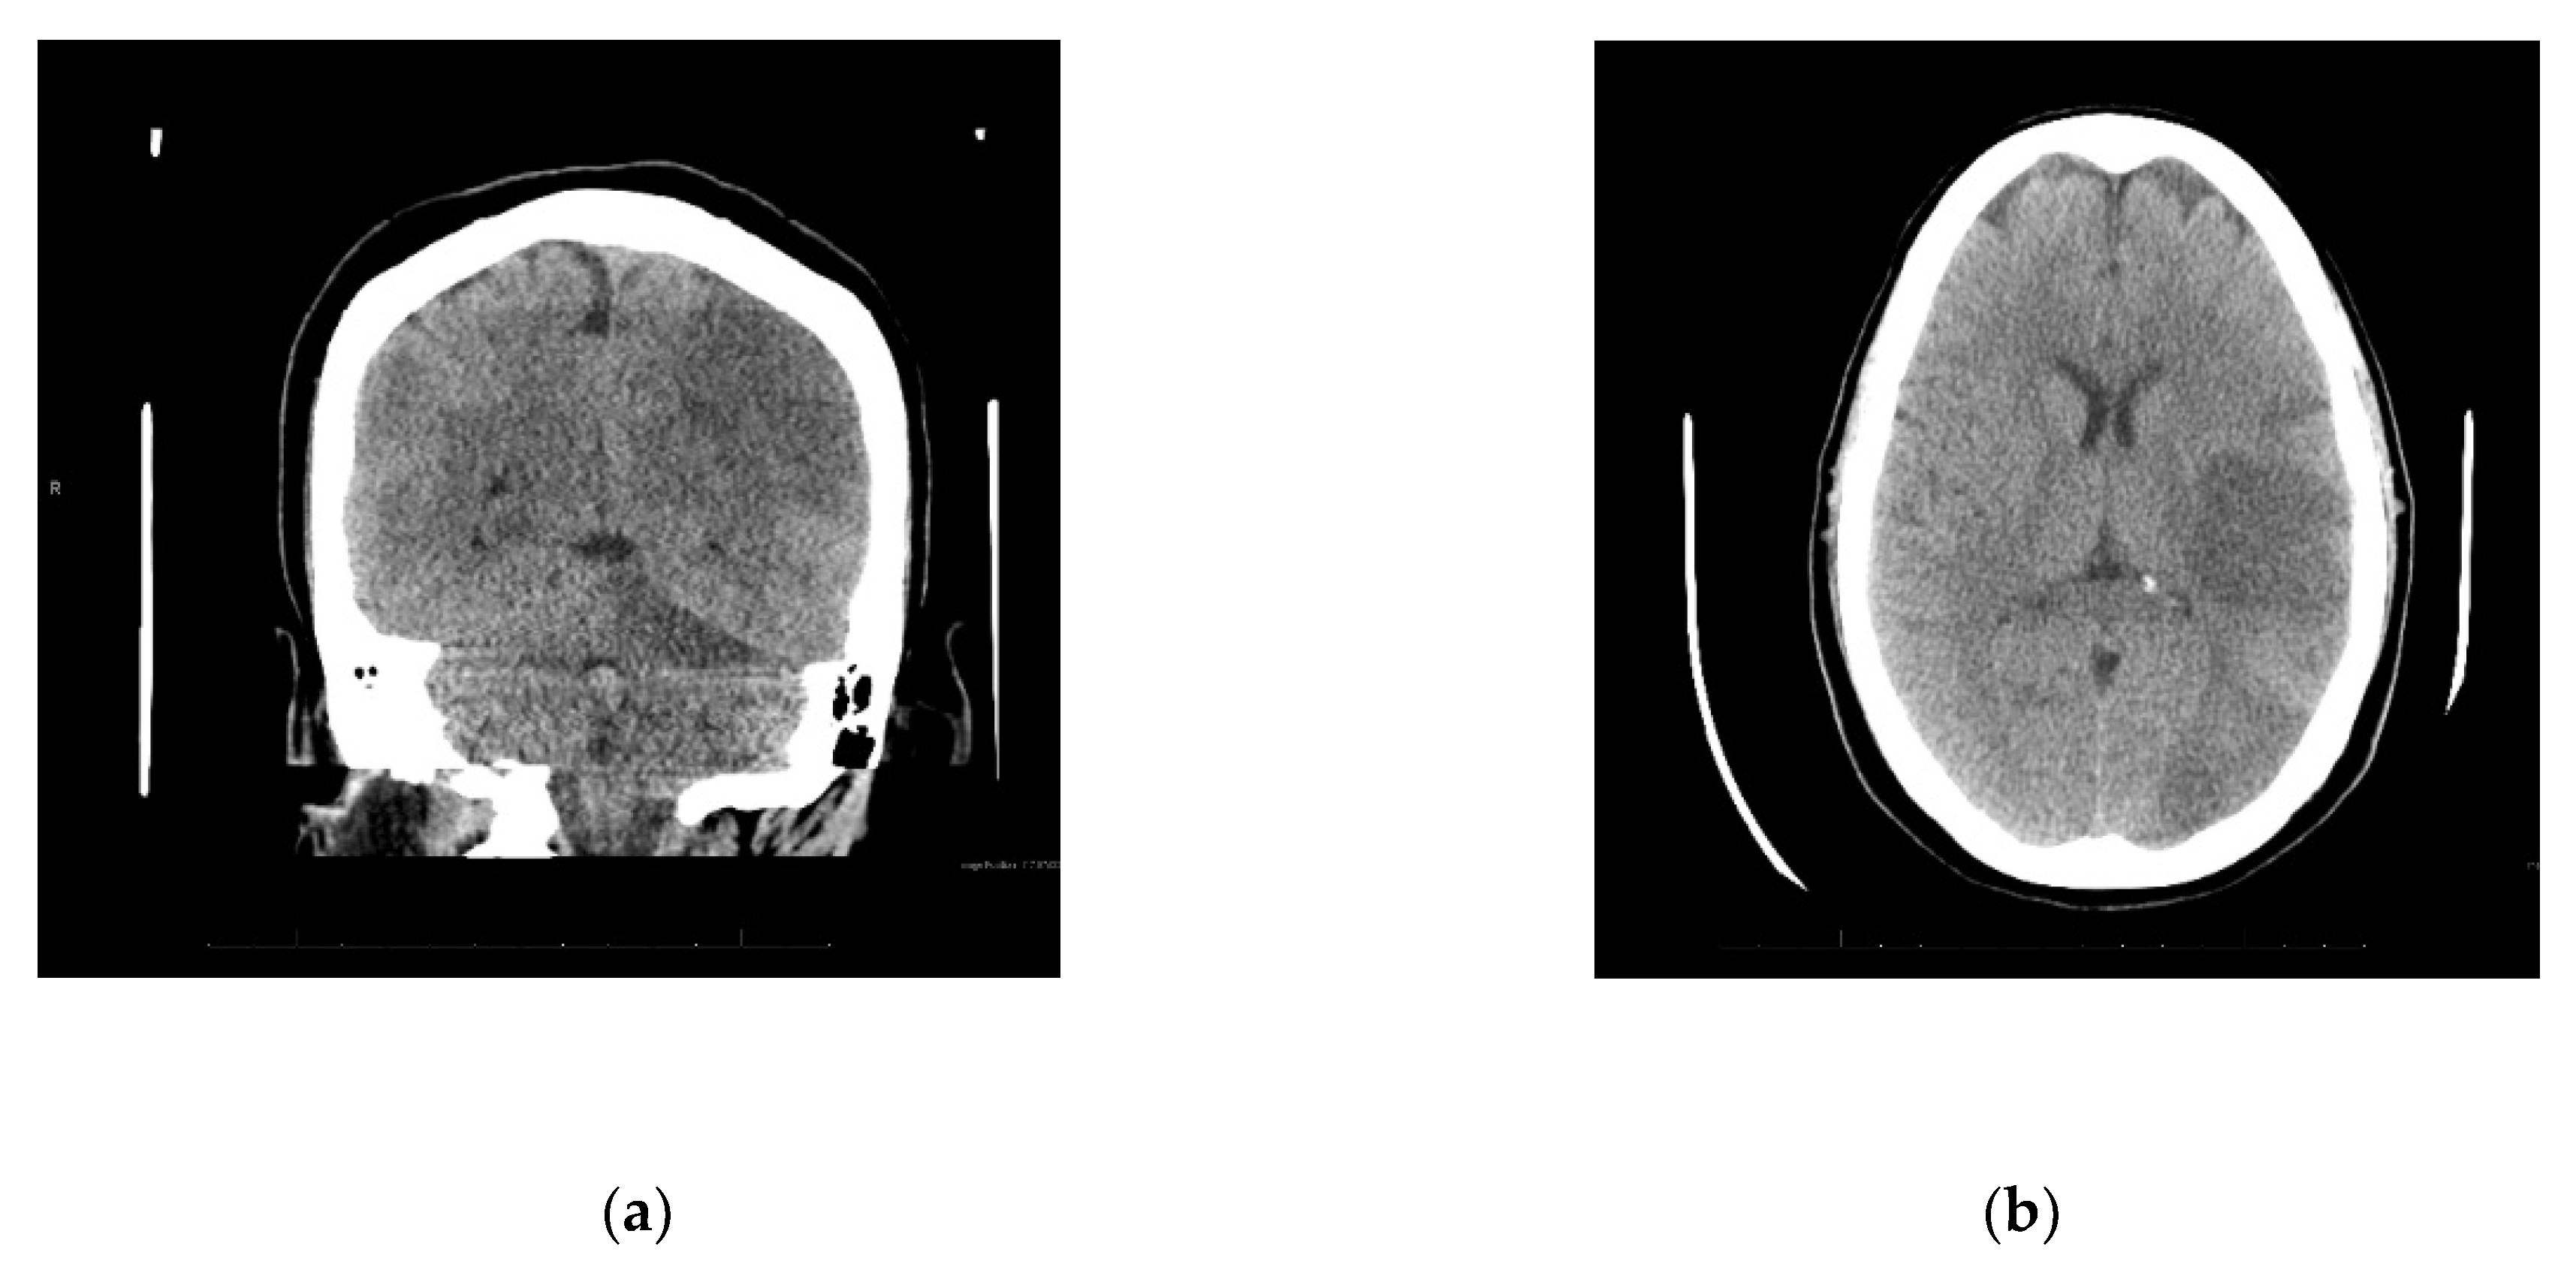

Upon arrival to the new facility, the patient was admitted to the Intensive Care Unit (ICU) and started on a Bumex drip and had a 2D-echocardiogram performed. The echocardiogram demonstrated a positive bubble study in the left atrium, suggesting a patent foramen ovale (PFO), severe pulmonary hypertension with a right ventricular mild dilation and reduced function. During the first three days of admission to the new hospital, the patient developed thrombosis of her right radial artery requiring a radial thrombectomy; she required a transfusion of one unit of packed red blood cells and one unit of platelets, plasmapheresis due to a possible TTP, and a Nicardipine (Cardene) drip. Dry gangrene in the distal right thumb developed due to a right radial artery thrombus (Figure 1b). The patient also demonstrated decreased responsiveness while on sedation vacation. A CT of the brain taken during this time reported multifocal acute infarcts involving the bilateral cerebral hemispheres and the left cerebellar hemisphere, given involvement of multiple vascular territories (Figure 2). A CT arteriogram of the brain and neck with IV contrast demonstrated an incomplete occlusive filling defect of the proximal internal jugular vein, raising concern for a partial thrombosis.

Four weeks after initial presentation to the emergency department, a neurocritical care evaluation reported the left posterior middle cerebral (MCA) and posterior cerebral (PCA) arteries, and right PCA and left superior cerebellar artery (SCA) infarcts. The report suggested severe encephalopathy. A CT angiogram of the head and neck showed no large vessel occlusion or significant steno-occlusive disease. Venous dopplers of the lower extremities was positive for a right external iliac vein non-occlusive deep vein thrombosis (DVT) for which she received an IVC filter. The patient had developed flaccid quadriplegia during hospitalization over the past month. She remains sedated on propofol and fentanyl and is poorly responsive when sedation is held.

Figure 2. (a) Diffuse infarcts; (b) Temporal and occipital lobe infarcts.